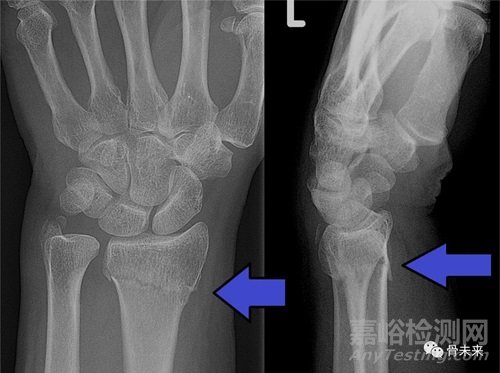

關(guān)于橈骨遠(yuǎn)端骨折

橈骨遠(yuǎn)端骨折是一種常見的上肢損傷,其治療方法多種多樣、發(fā)展迅速。但是,自從出現(xiàn)了掌側(cè)鎖定鋼板(volar locked plating,VLP)之后,臨床上多選擇用手術(shù)治療。

除了VLP之外,其他的固定方式包括:經(jīng)皮穿針固定、背側(cè)鋼板、背側(cè)橋接鋼板、骨塊特異性固定、外固定架固定(跨關(guān)節(jié)和不跨關(guān)節(jié))等等。不過,雖然手術(shù)固定的方式多種多樣,但術(shù)后的并發(fā)癥發(fā)生率依然很高,其中屈肌腱及伸肌腱損傷是最常見的并發(fā)癥。